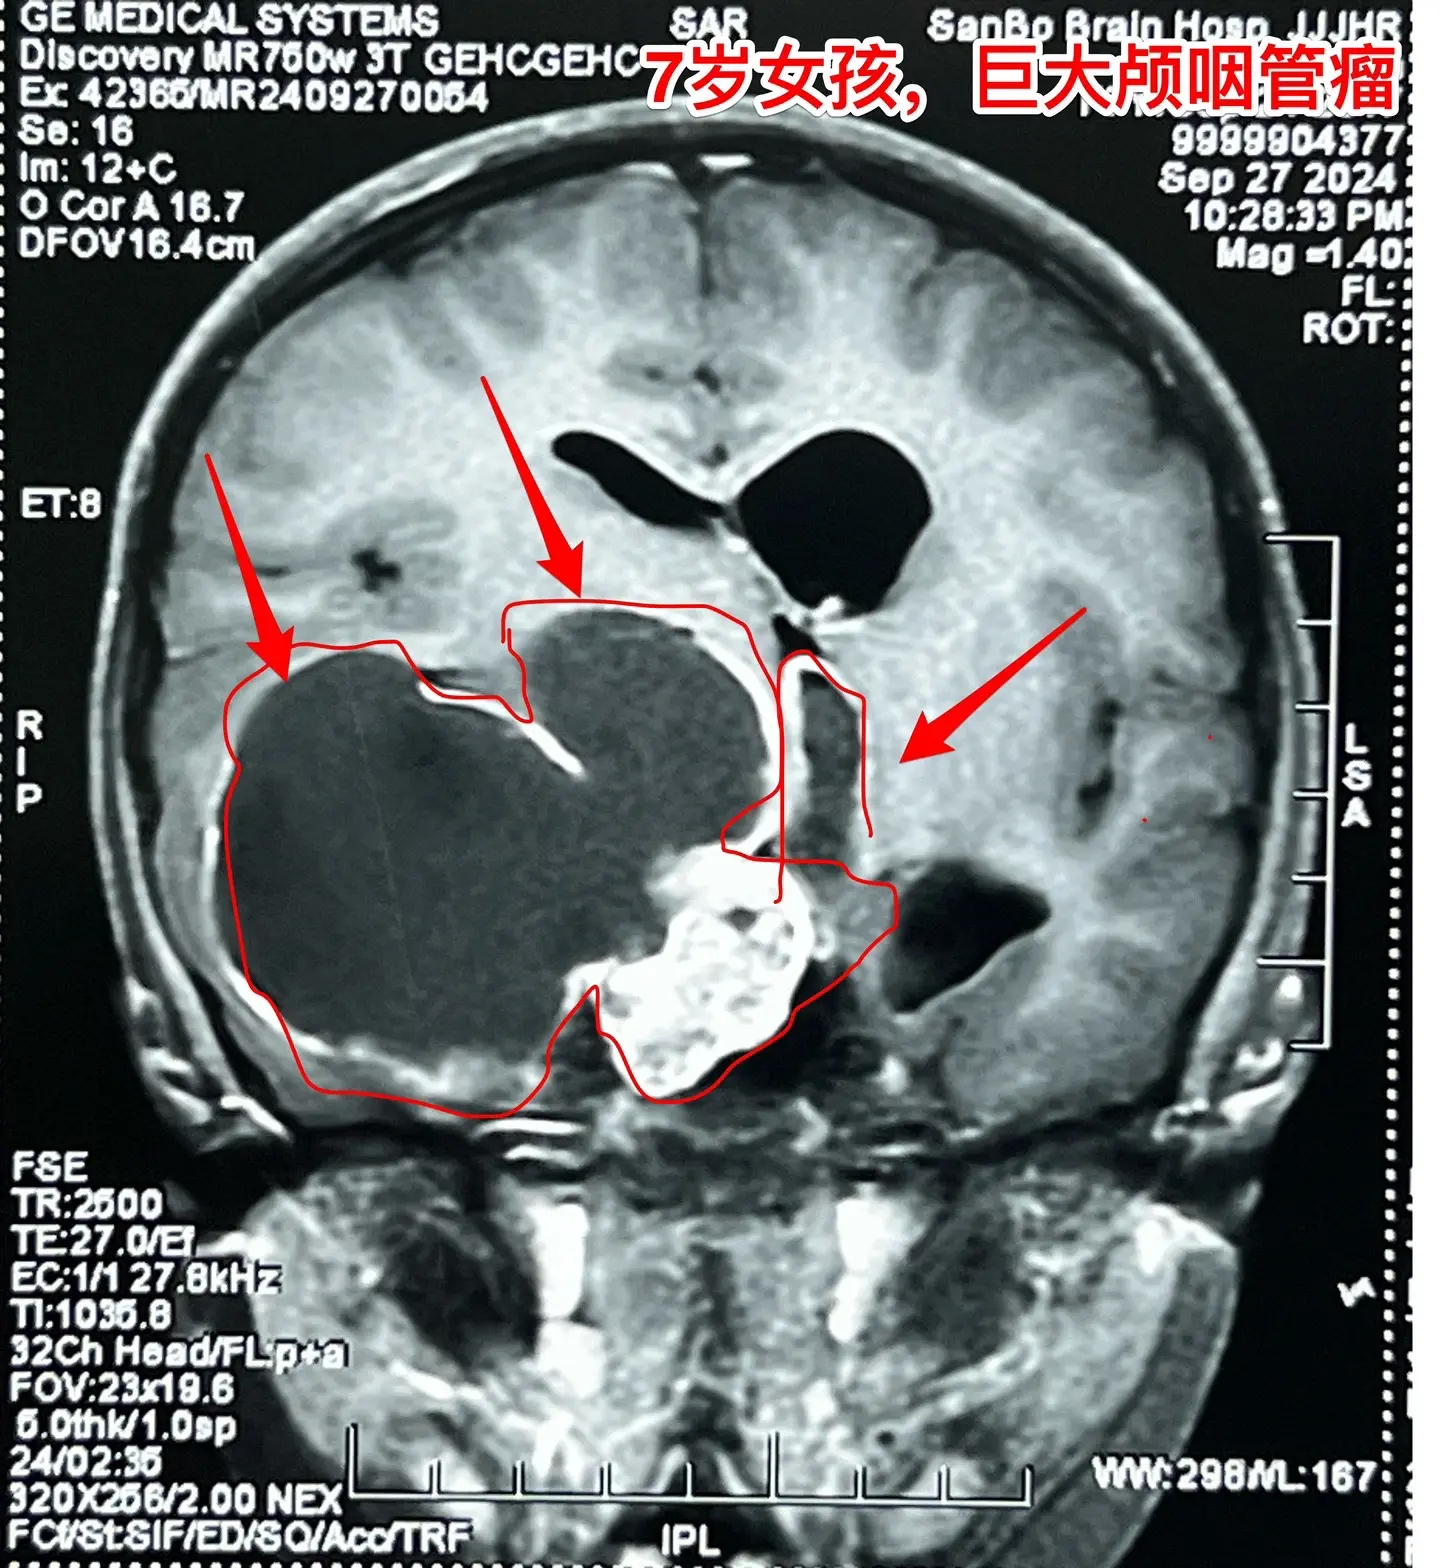

漳州市女孩子脑部长了巨大的颅咽管瘤。7岁漳州市女孩子,入院前两个月经常出现呕吐,按胃肠疾病治疗无效。入院前20天出现左侧上下肢活动力弱,伴有左上肢抖动。在厦门某医院经CT检查发现是脑部肿瘤。 从头CT可以看出这是典型的颅咽管瘤,鞍区有很大的钙化团块,小块肿瘤侵入第三脑室,肿瘤囊向右侧颞部及基底节区生长并有推挤压迫效应。手术有难度啊! 我们的手术入路设计思路:肿瘤起源点在中线,有大块钙化,是手术的难点,故以中线方向为主攻方向,争取将肿瘤的起源点及钙化完全切除!而向右侧颞部生长的肿瘤囊虽然体积大,只是肿瘤的扩张产物,切除的难度并不大,故右侧裂方向只需迂回攻击即可搞定。按这个思路设计手术方案后,手术中也有出乎意料的环节。鞍上的肿瘤钙化块又大又硬,花费很大精力才能将其体积减小,从视交叉前间隙取出。肿瘤囊从颈内动脉下方侵入颞叶,一部分囊自颞部向中线方向返折嵌入到基底节区。如术前所料,这部分囊性肿瘤切除难度不是太大。肿瘤最终得到完全切除,手术后患儿精神好,四肢活动自如。